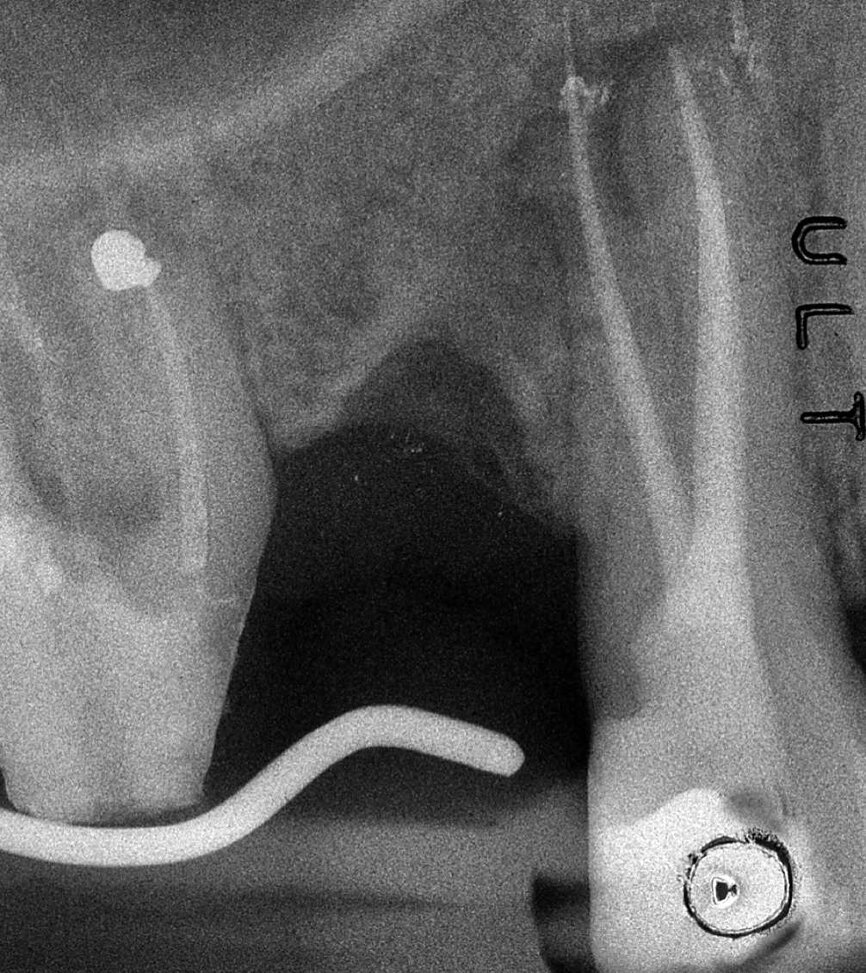

Dans la prémolaire maxillaire présentée dans les figures 5 et 6, le fistulogramme indique la présence d’une lésion apicale, qui s’étend en direction coronaire jusqu’au tiers moyen de la racine. La décision clinique pourrait donc s’orienter vers un retraitement orthograde ; toutefois, le cliché CBCT nous donne une tout autre vision de la situation que celle de la radiographie, dans la mesure où il montre une lésion irréversible de la dent due à un traitement antérieur, et la nécessité de l’extraire.